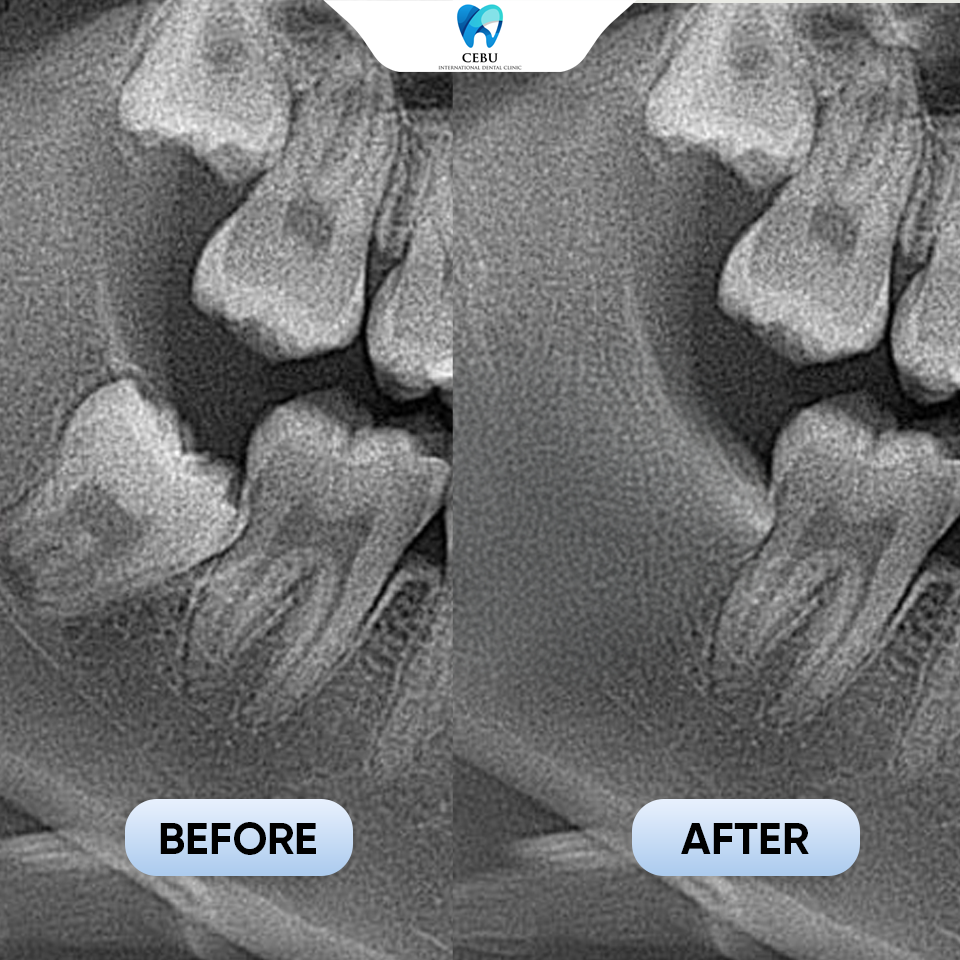

Serious dental risks you face when leaving wisdom teeth untreated today A Wisdom Tooth may seem harmless at first, but improperly erupted wisdom teeth can ...

Serious dental risks you face when leaving wisdom teeth untreated today A Wisdom Tooth may seem harmless at first, but improperly erupted wisdom teeth can lead ...